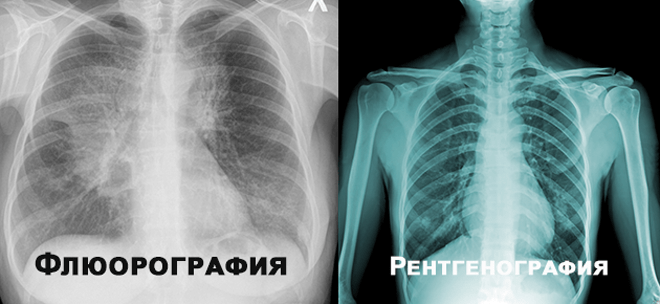

Флюорографія і рентген: різниця методів обстеження

Питання про флюорографія і рентген різниця доволі часто виникає серед пацієнтів, які стикаються з необхідністю проходження цих видів обстежень. Обидва вони є рентгенологічними методами діагностики, однак мають важливі відмінності, які варто знати. У цьому матеріалі ми розглянемо основні аспекти, які допоможуть зрозуміти, чому роблять флюорографію, а не рентген, в окремих випадках, і навпаки.

Флюорографія – це метод рентгенологічного обстеження, який застосовується головним чином для скринінгу захворювань органів грудної клітки, таких як туберкульоз або новоутворення. Її особливістю є менше променеве навантаження на організм пацієнта порівняно з традиційним рентгеном. У флюорографії використовуються спеціальні флюоресцентні екрани і цифрова обробка зображення, що дозволяє зменшити рівень опромінення.

Рентгенографія – це більш загальний метод, який може використовуватись для дослідження різних частин тіла. На відміну від флюорографії, рентген дає більш детальне і точне зображення, яке може бути необхідним для діагностики складних захворювань кісткової системи, травм, або патологій внутрішніх органів.